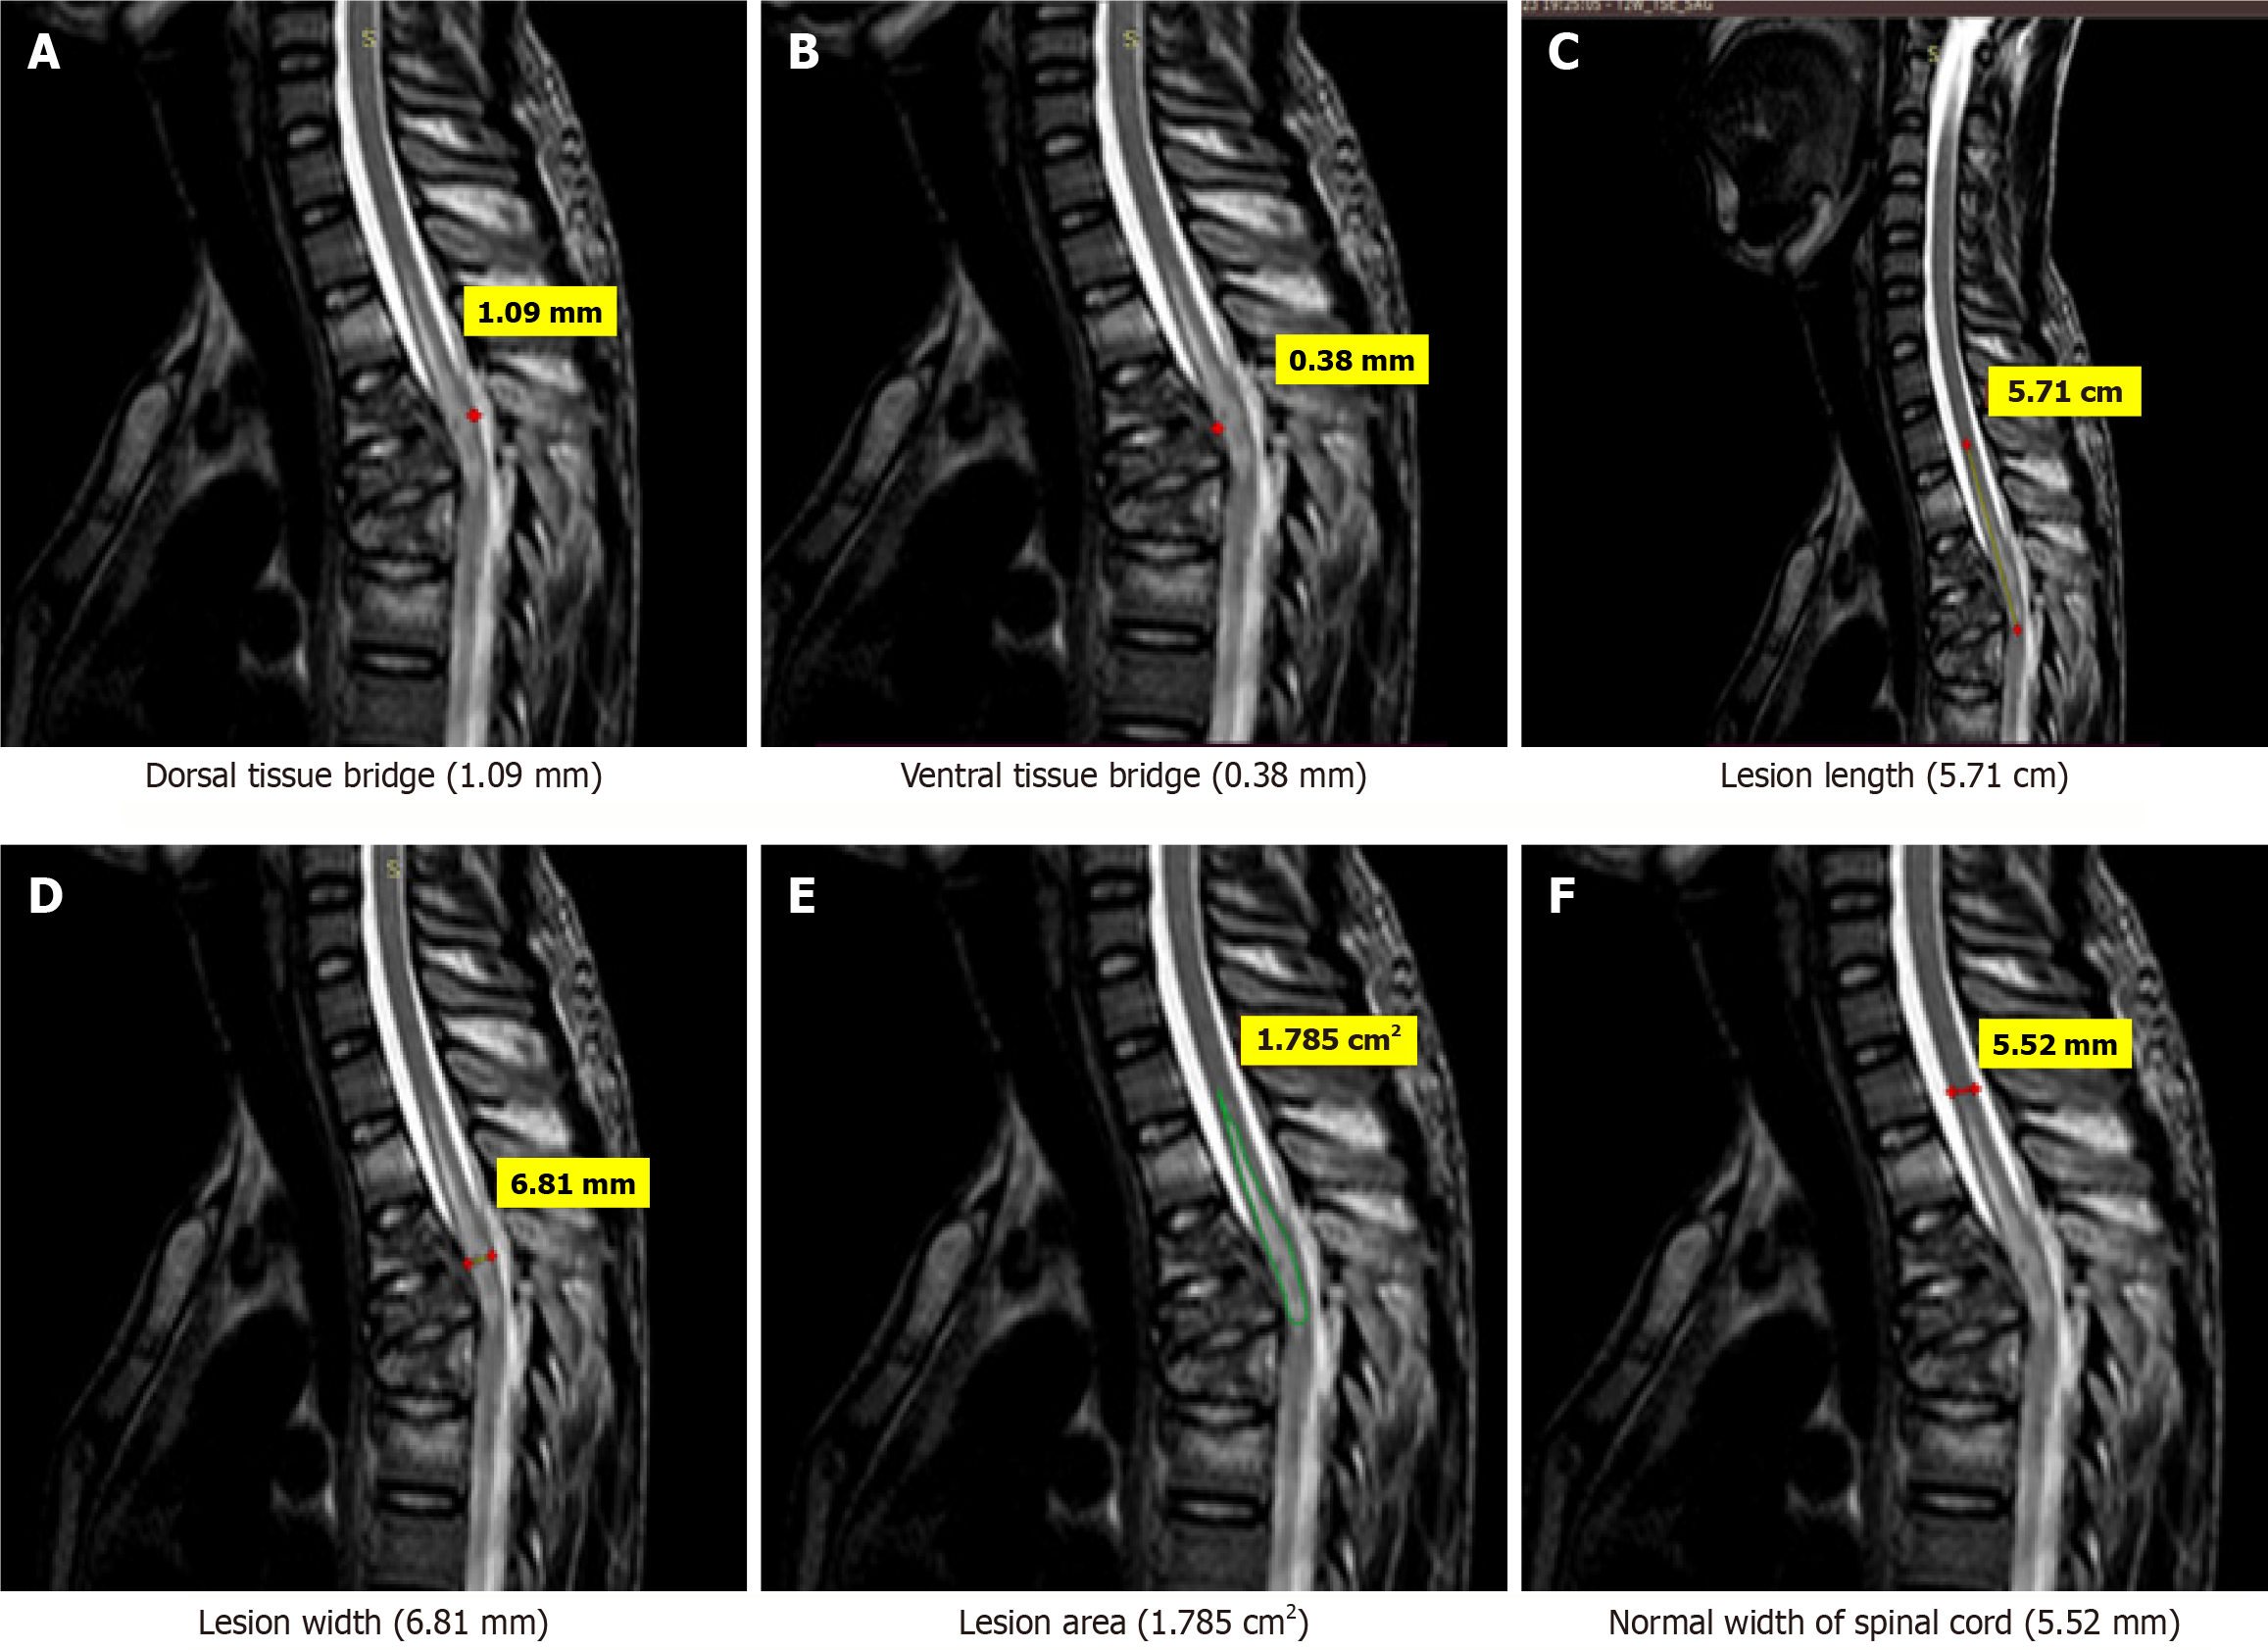

Figure 1 Magnetic resonance imaging T2-weighted sagittal images of an 18-years-old patient who sustained trauma to thoracic spine (D10-D11) with ASIA grade C.

A: Dorsal tissue bridge (1.09 mm); B: Ventral tissue bridge (0.38 mm); C: The lesion length (5.71 cm); D: Lesion width (6.81 mm); E; Lesion area (1.785 cm2); F: Normal width of spinal cord (5.52 mm).